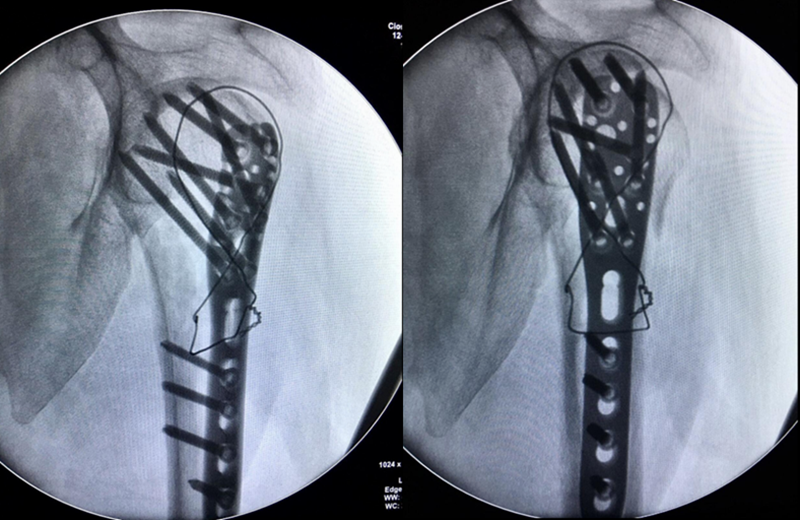

图17 术中

术中C-臂检测:

图18 肱骨距螺钉固定确切

术中大幅度肩关节屈伸与外展内收活动,提示骨折坚强固定。